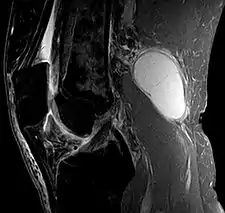

| Ultrasound image of Baker's cyst | |

| Diagnostic method | Confirmed by ultrasound or MRI[3] |

Risk factors include other knee problems such as osteoarthritis, meniscal tears, or rheumatoid arthritis.[1][3][4] The underlying mechanism involves the flow of synovial fluid from the knee joint to the gastrocnemio-semimembranosus bursa, resulting in its expansion.[1] The diagnosis may be confirmed with ultrasound or magnetic resonance imaging (MRI).[3]

Diagnosis is by examination. A Baker's cyst is easier to see from behind with the patient standing with knees fully extended. It is most easily palpated (felt) with the knee partially flexed. Diagnosis is confirmed by ultrasonography, although if needed and there is no suspicion of a popliteal artery aneurysm then aspiration of synovial fluid from the cyst may be undertaken with care. An MRI image can reveal presence of a Baker's cyst.